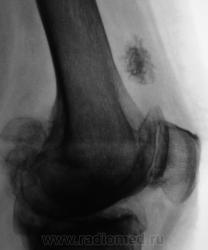

Пациентка направлена на рентгенографию коленного сустава с диагнозом "Деформирующий артроз".

Выраженный деформирующий артроз, множественные хонтроматозные тела в полости сустава.